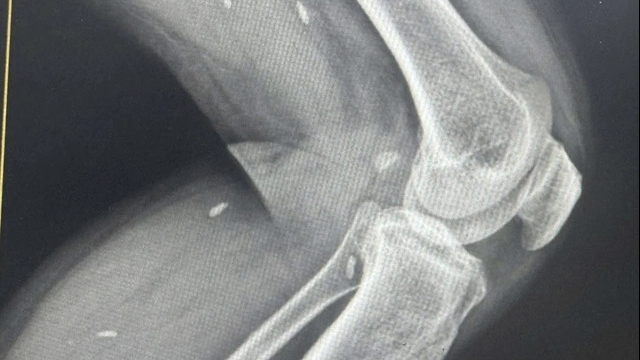

Thủy Tiên tình cờ phát hiện mắc ung thư vú vào tháng 6/2019 sau khi sờ thấy cục hạch bằng đầu ngón tay ở ngực. Ban đầu bác sĩ chẩn đoán u xơ, chỉ định tiểu phẫu cắt u, nhưng kết quả sinh thiết khiến cô gái 19 tuổi ngã quỵ khi biết mình mắc ung thư vú giai đoạn 2a.